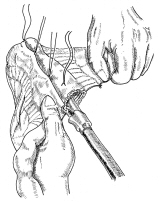

器械吻合器テクニックあれこれ

あのころ、実用化されたばかりの自動吻合器の使用上の「コツ」シリーズ。